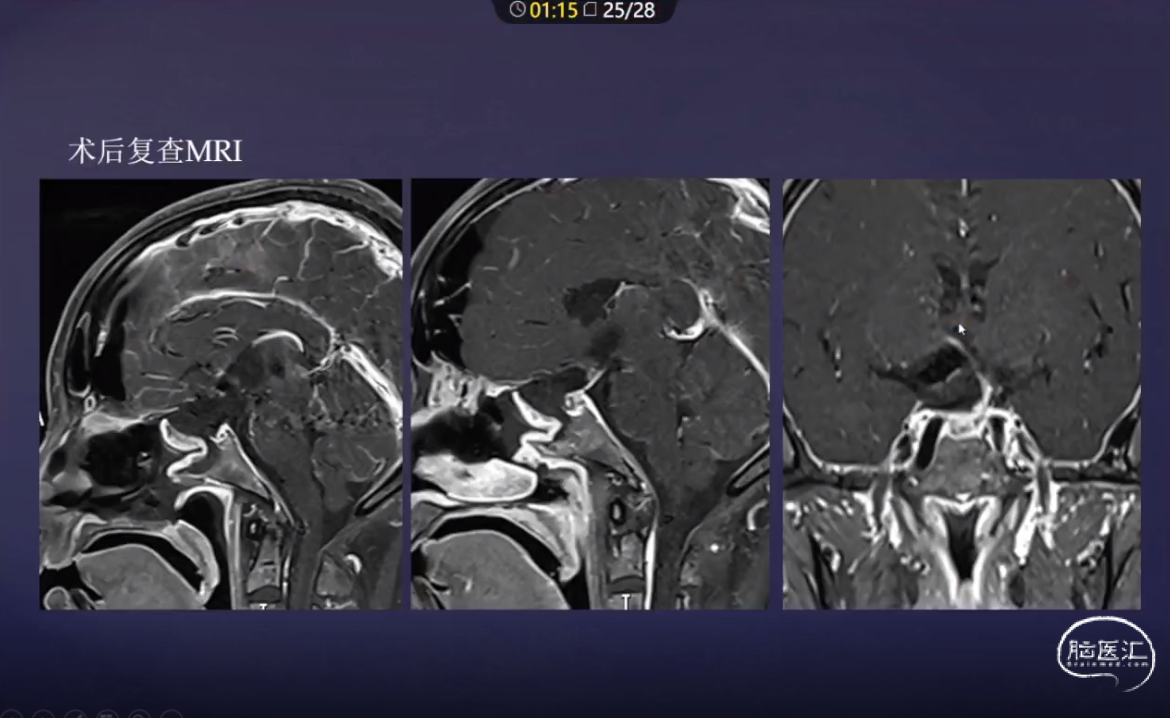

洪涛教授:经鼻内镜颅咽管瘤切除术

本文从内镜下颅咽管瘤分型,下丘脑损伤分级,不同分型颅咽管瘤术中要点,结合病例多角度为大家分享经鼻内镜颅咽管瘤切除术。